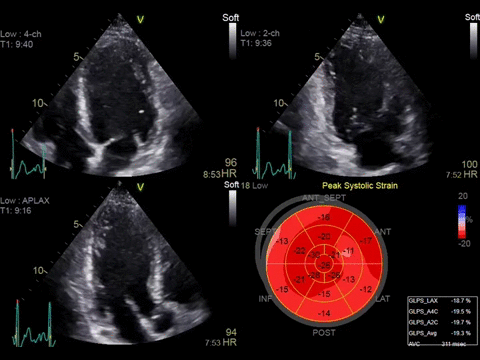

• Автоматическая оценка регионарной сократимости миокарда левого желудочка с расчетом большой группы параметров с помощью функции Automated Function Imaging (AFI).

• Протоколы AFI Stress, позволяющие получать стандартные апикальные проекции в двумерном режиме и рассчитывать регионарную и глобальную продольную деформацию миокарда на всех уровнях нагрузки.

• Функция 4D Strain для расчета глобальной и регионарной деформации миокарда на основе алгоритма пространственного спекл-трекинга, отображаемая в виде диаграммы «бычий глаз».